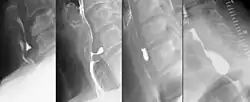

Radiologen teilen die Zenker-Divertikel nach Brombart in vier Stadien zunehmender Schwere ein:

- Stadium 1 ist eine dornenförmige, 2–3 mm lange Nischenbildung, die auch nicht immer sichtbar wird.

- Divertikel im Stadium 2 sind 7–8 mm groß und keulenförmig.

- Divertikel im Stadium 3 sind über 10 mm groß, sackförmig und nach unten umgebogen.

- Im Stadium 4 komprimiert das Divertikel die Speiseröhre und behindert sichtbar dessen Kontrastmittelpassage.[3]

Die Diagnostik erfolgt bei entsprechenden Symptomen mit der Endoskopie und Röntgenaufnahmen mit Kontrastmittel. Sobald ein Patient Schluckstörungen bemerkt, sollte er sich in fachärztliche Betreuung begeben, denn diverse Erkrankungen der Speiseröhre können diese Beschwerden hervorrufen. Danach sollte eine genaue Inspektion von Mund und Rachen des Patienten erfolgen und der Hals nach vergrößerten Lymphknoten oder Weichteilveränderungen abgetastet werden. Je nach Verdachtsdiagnose wird eine Spiegelung der Speiseröhre durchgeführt und gleichzeitig im Bereich auffälliger Schleimhautbereiche eine Gewebeprobe entnommen. Ergänzend, vor allem bei Divertikeln, wird eine Röntgenuntersuchung der Speiseröhre mit flüssigem Kontrastmittel durchgeführt, die auch Bewegungsstörungen der Speiseröhrenwand zeigen kann. Handelt es sich bei der Erkrankung um einen Tumor, ist es unter Umständen notwendig, eine zusätzliche CT- oder MRI-Untersuchung durchzuführen, um seine Ausdehnung und Lage im Brustkorb zu sehen. Unter Umständen ist auch eine Voruntersuchung durch einen Hals-Nasen-Ohren-Arzt notwendig, der die Funktionsfähigkeit eines wichtigen Nervs im Bereich des Kehlkopfes überprüfen muss. Je nach Vorerkrankungen und Alter des Patienten werden auch Ultraschalluntersuchungen am Herzen sowie eine Lungenfunktionsprüfung durchgeführt. Bei einem Zenker-Divertikel ist die Indikation zur Operation gegeben, völlig unabhängig davon, wie stark die Beschwerden des Patienten sind, denn die Komplikationsrate ist gering.